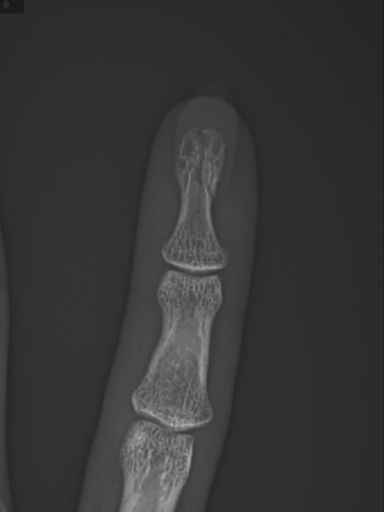

I cyk i po paluszku Edit: złamany 🙃